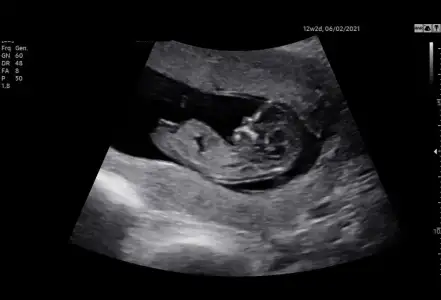

Teşekkür ederimKız gibi oncekide 13+3 de kız gibi ama emin olamadım![]()

Kızım olacak. tahminin tuttu. Bir tek sen dedin kız diye. Kesin olarak hayırlısıyla üçüncü çocuğum kız olacak. TeşekkürlerKeşke.. erkek dedi ama kesin 14. Hafta da bakarız dedi. Video var sadece